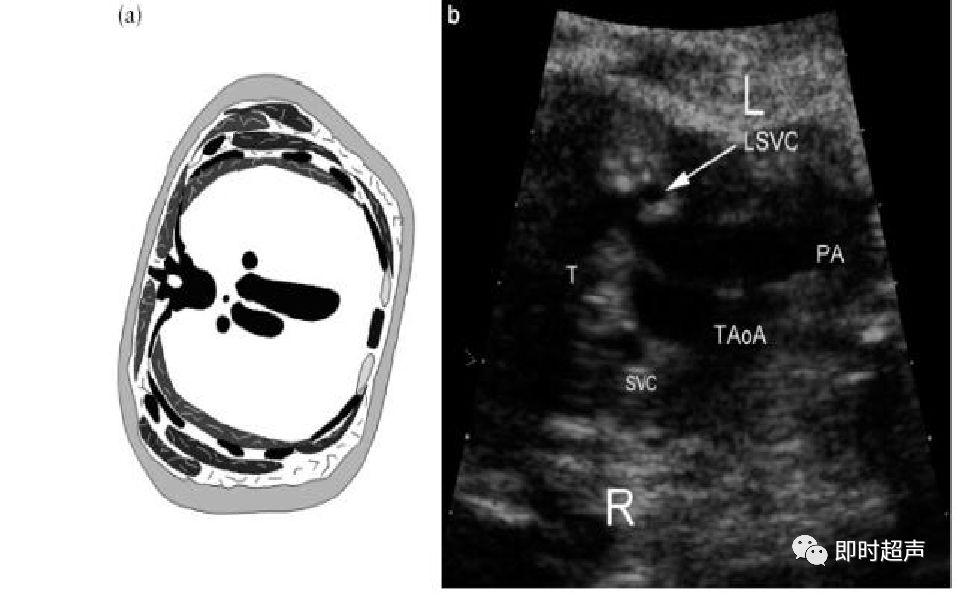

以CT横断面解剖为例

(这是从胎儿头侧往脚侧观看的解剖示意图)

(这是从胎儿脚侧往头侧观看的解剖示意图)